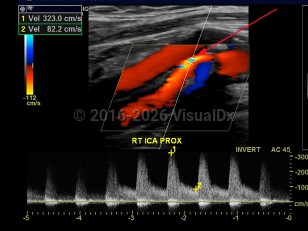

Imaging Studies image of Carotid artery stenosis - imageId=7878398. Click to open in gallery.  caption: '<span>Color and spectral Doppler image of the proxima right internal carotid artery demonstrating >70% stenosis.</span>'

Color and spectral Doppler image of the proxima right internal carotid artery demonstrating >70% stenosis.